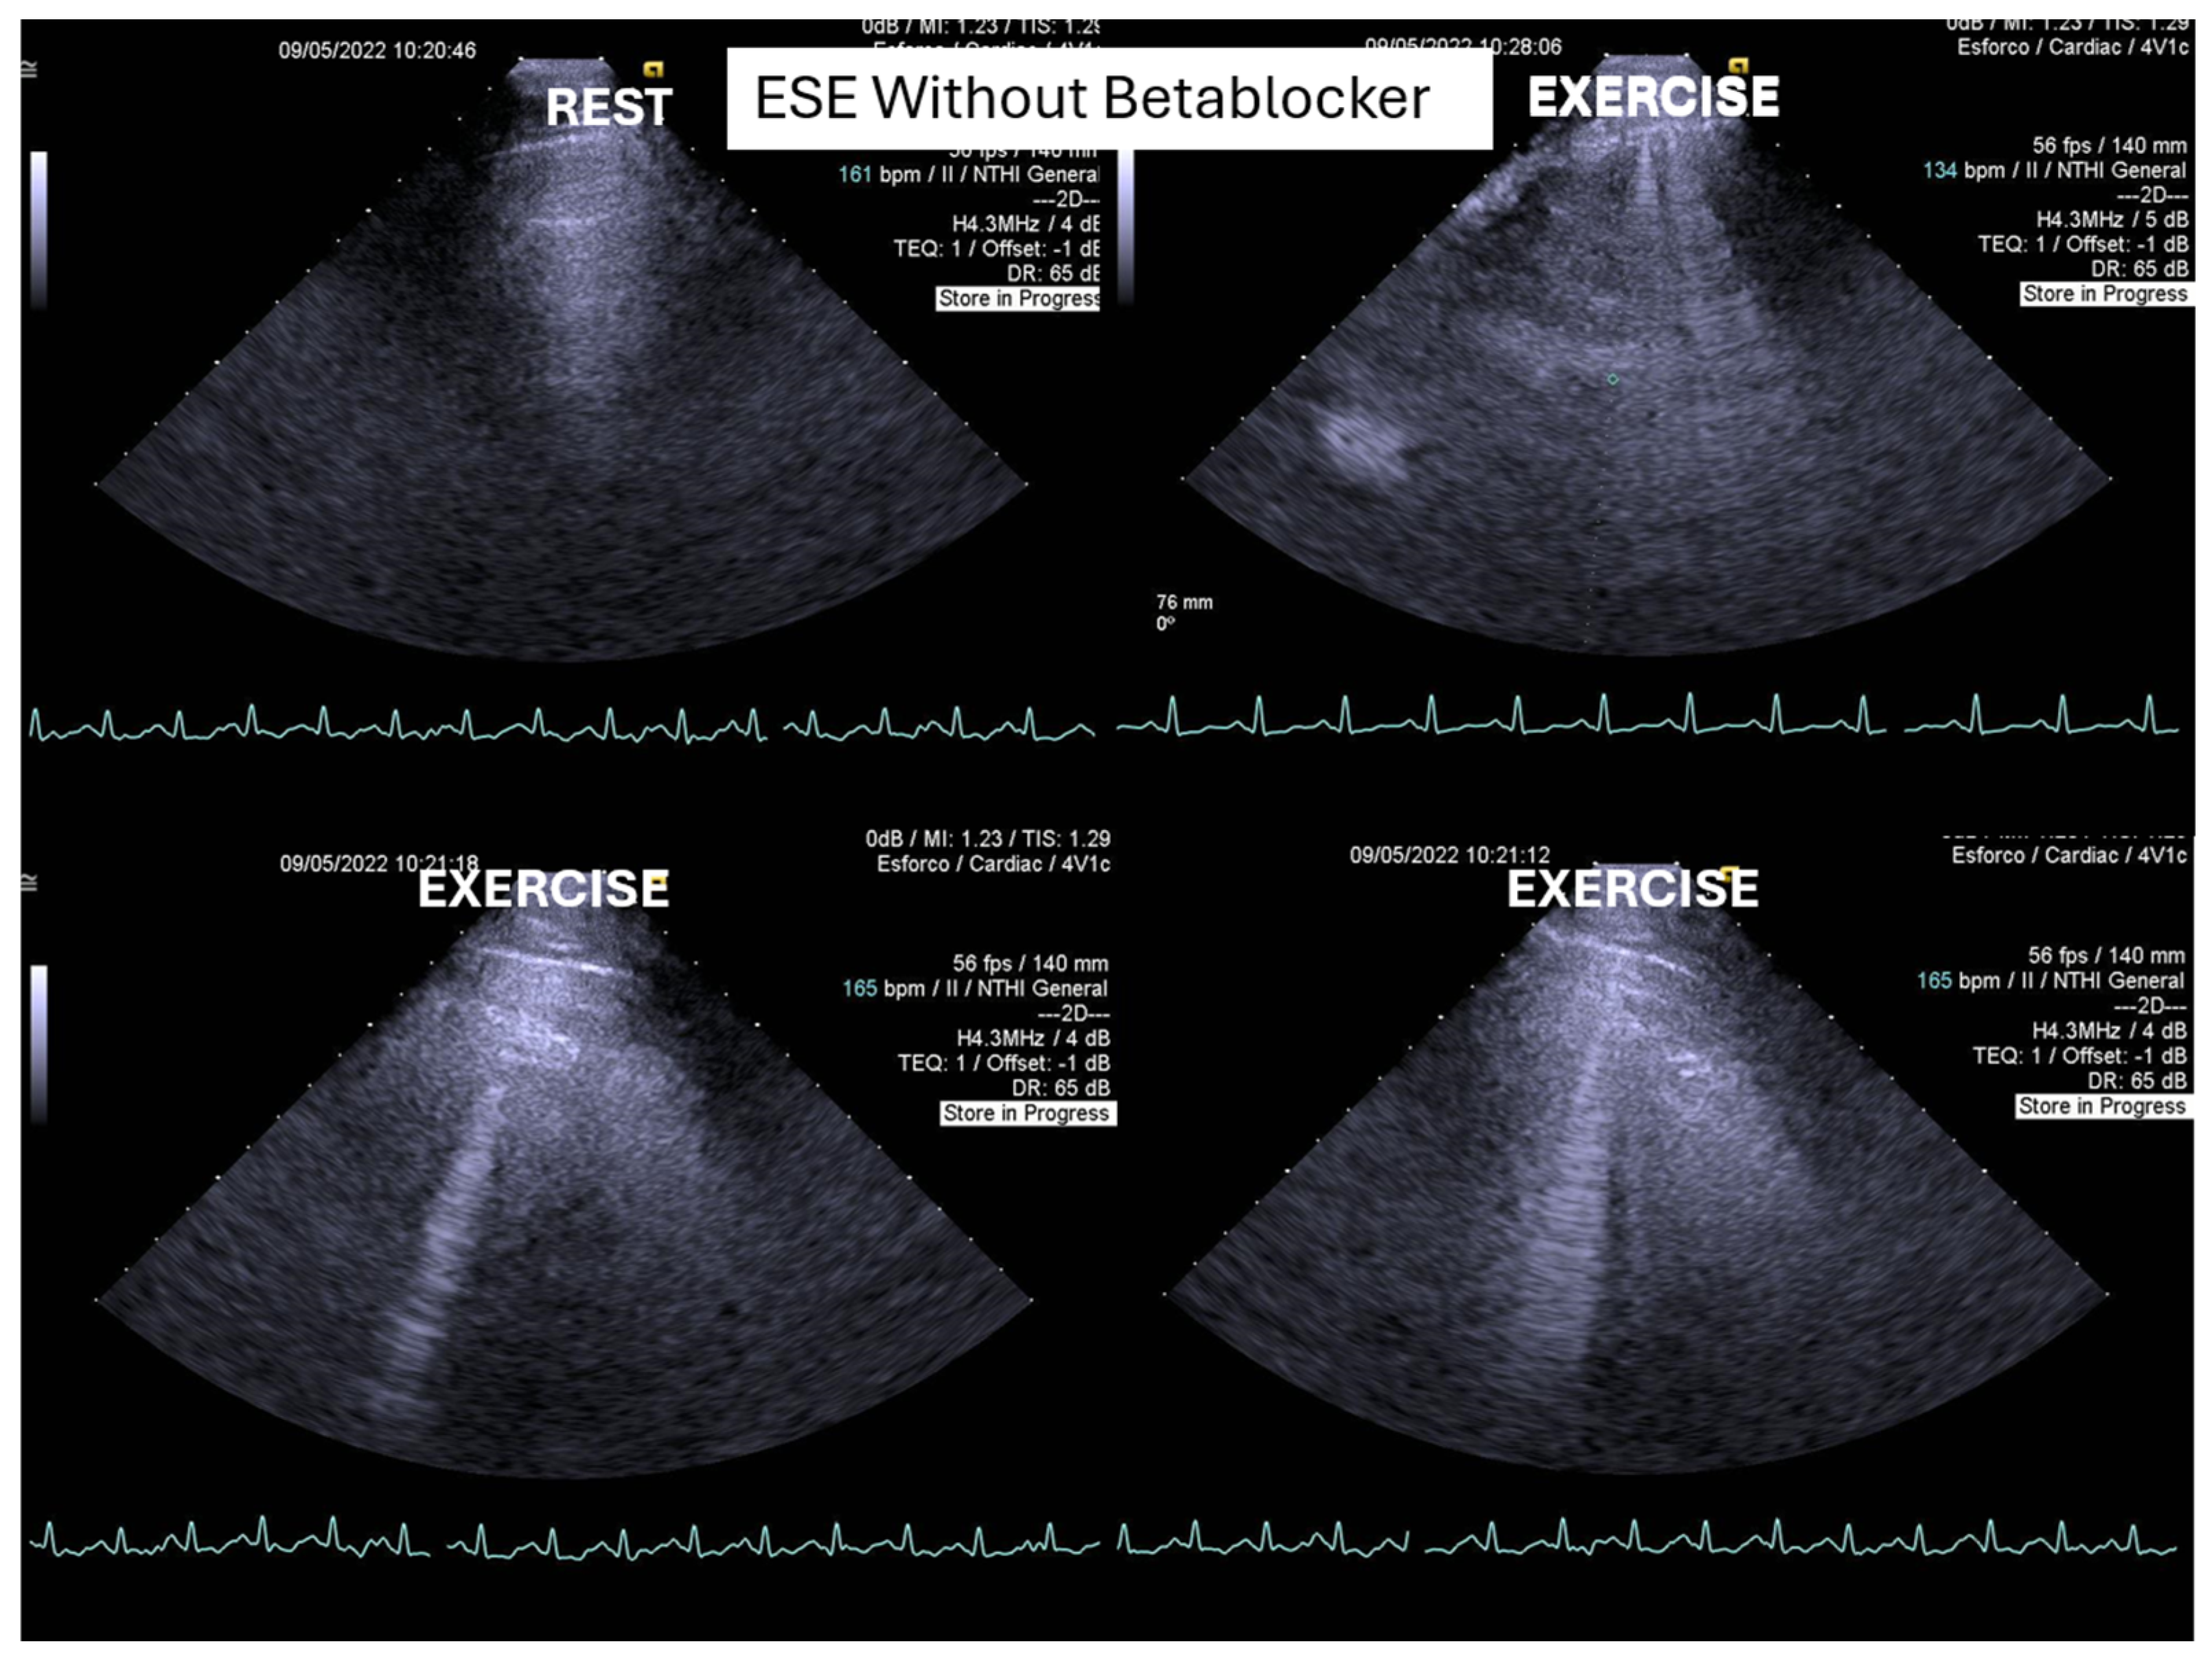

Figure 2.

This figure depicts an intraventricular pressure gradient observed during exercise in an adolescent presenting severe exertional dyspnea, accompanied by pronounced systolic anterior motion (SAM) of the mitral valve.

On the resting echocardiogram, all the exams were considered normal with and without beta-blockers. No wall motion abnormalities were detected in any of the exams, with or without beta-blockers. In the complete group, IVPG (Figure 1) at peak exercise on the first assessment was 105 ± 38 mmHg, with mitral valve SAM in 28 adolescents (Figure 2). Among the 29 adolescents treated with beta-blockers, IVPG was 58 ± 32 mmHg, p < 0.0001.

In our study, beta-blocker therapy was associated with reductions in heart rate, exercise-induced ST-segment alterations, systolic blood pressure, and, consequently, peak heart rate–systolic blood pressure product (HR × SBP). The incidence of intraventricular gradients (IVGs) (Figure 1) and systolic anterior motion (SAM) of the mitral valve (Figure 2) during exertion also decreased significantly. These hemodynamic improvements were accompanied by a notable reduction in symptoms during exercise testing and follow-up

The condition was managed using bisoprolol, which led to clinical improvements and substantial reductions in intraventricular pressure gradients (IVPGs). It has long been recognized that small intraventricular pressure gradients are a common phenomenon. Three mechanisms have been proposed to explain their significant increase during exercise: (1) an amplification of non-obstructive physiological gradients, (2) end-systolic obstruction due to mid-cavity obliteration of the ventricle, and (3) mid-systolic obstruction caused by systolic anterior motion (SAM) of the mitral valve, which restricts blood ejection [2,3].